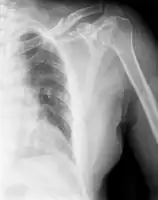

| X-ray of a left clavicle fracture | |

The basic method to check for a clavicle fracture is by an X-ray of the clavicle to determine the fracture type and extent of injury. In former times, X-rays were taken of both clavicle bones for comparison purposes. Due to the curved shape in a tilted plane X-rays are typically oriented with ~15° upwards facing tilt from the front. In more severe cases, a computerized tomography (CT) or magnetic resonance imaging (MRI) scan is taken. However, the standard method of diagnosis through ultrasound imaging performed in the emergency room may be equally accurate in children.[6]